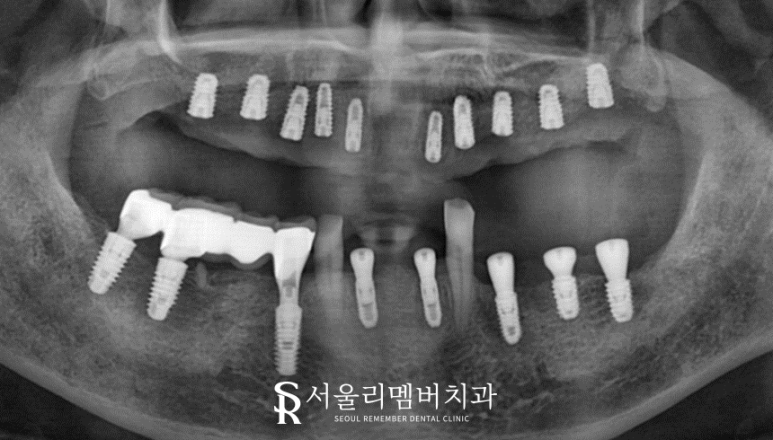

나머지 치아들은 잔존 조직 없이 깨끗하게 발치를 끝내고

이어서 뼈이식과 임플란트 식립에 들어갔습니다.

제가 여러 번 말했었는데요. 식립 개수가 많은 분들은 한 번에 모든 곳을 심게 되면 무리가 갑니다.

특히 서울대입구역 전체 임플란트의 경우는 주환자의 연령대가 높은 편이기도 하죠.

시간은 좀 걸릴지라도 안전한 방법을 택하여 픽스처를 심어드렸습니다.

구강이 별로 좋지 않은 분이어서 골 유착이 잘 이루어질 수 있을까 걱정이 되었는데요.

다행히 별문제 없이 단단히 고정된 모습입니다.

이제 여기에 최종 보철만 올려두면 모든 치료가 마무리되겠군요.